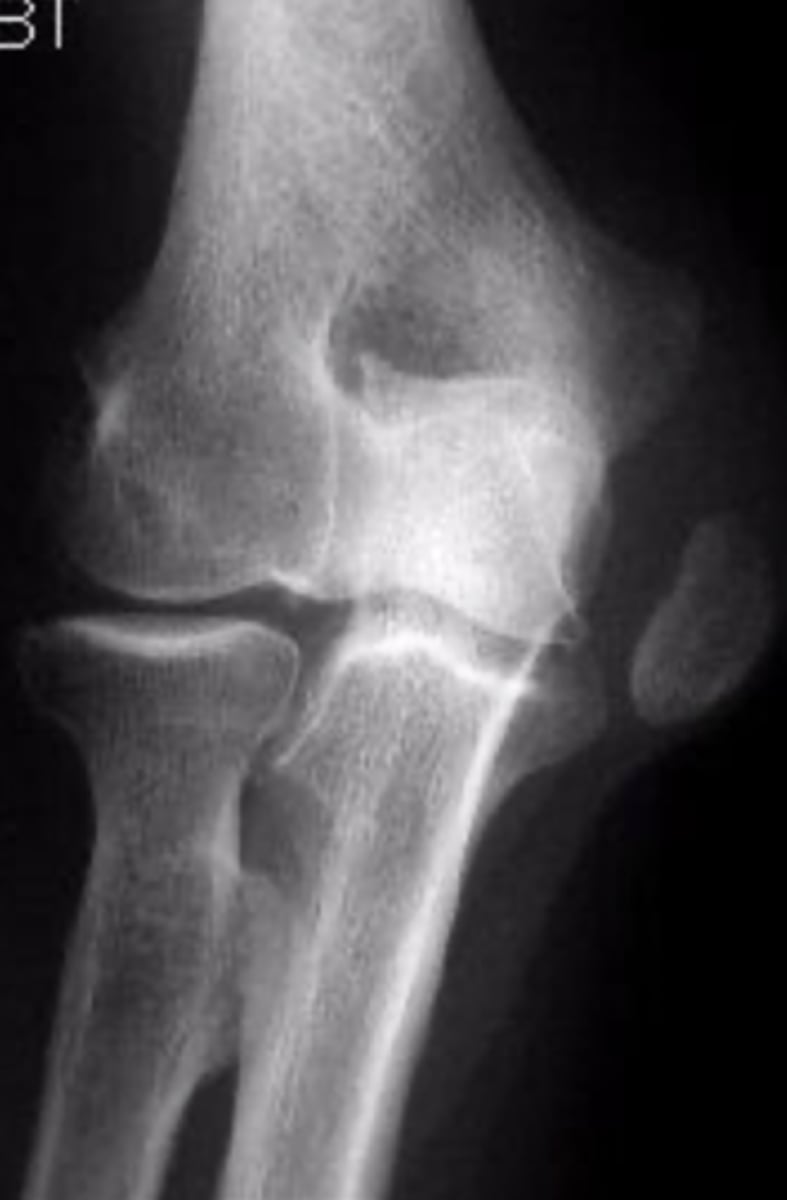

Medial epicondyle avulsion fracture

What is the issue?